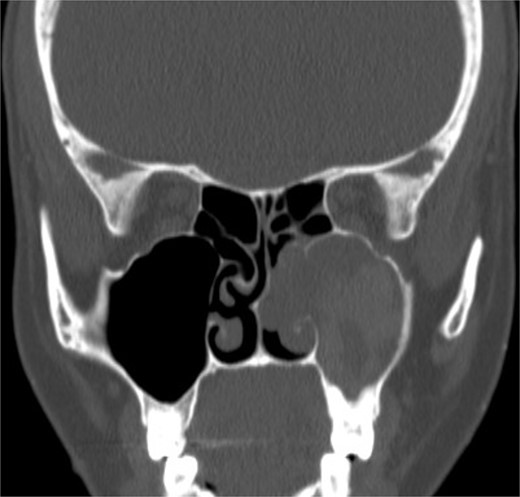

Isolated maxillary fungal ball

A 30-year-old lady presented to the clinic with a complaint of right facial pain, recurrent rhinorrhea with post-nasal discharge, nasal endoscopic examination was unremarkable. A non-contrast computed-tomography scan (NCCT) of the paranasal sinuses (Fig. 1) was suggestive of isolated right fungal maxillary fungal ball (FB). The patient underwent endoscopic sinus surgery (ESS) with (Fig. 2) right middle meatal antrostomy and removal of fungal debris. The patient was followed up regularly and remained symptom free.

Axial (A) and coronal (B) images of a nonenhanced CT scan of the paranasal sinuses showing right maxillary sinus complete heterogenous opacification.